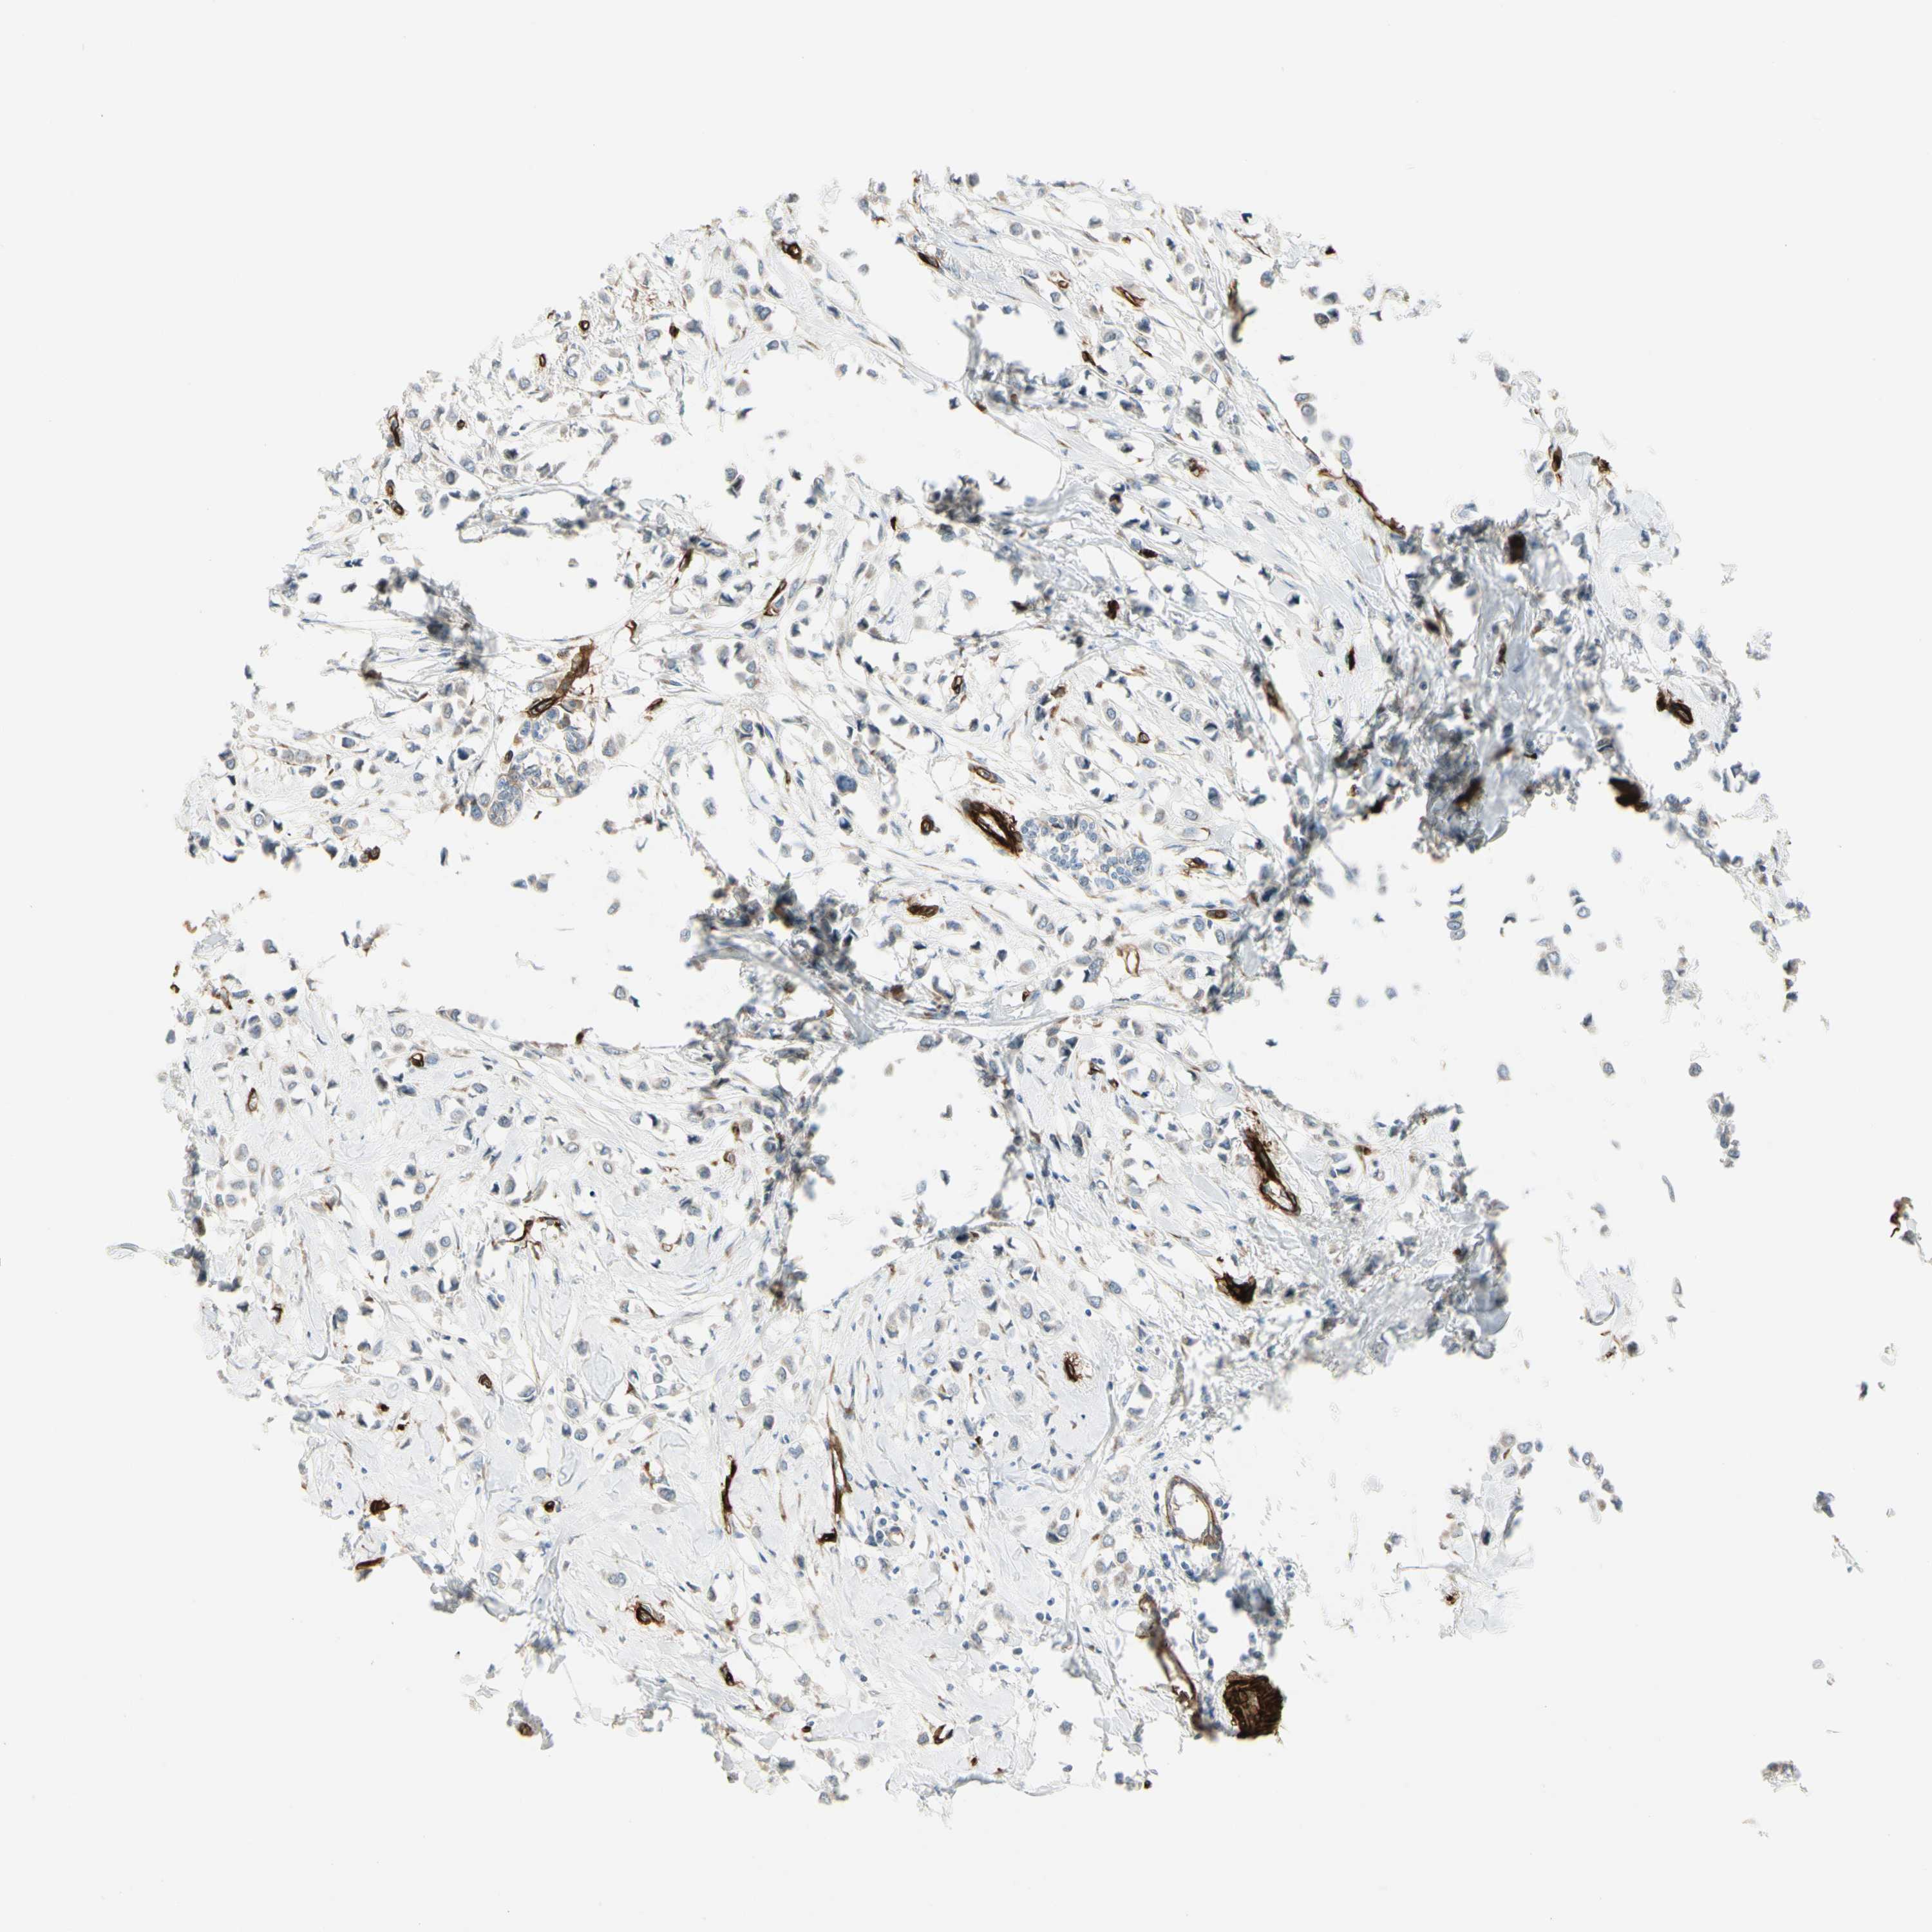

CANCER BREAST CANCER Show tissue menu

BRCA TCGA BRCA VALIDATION PROTEIN EXPRESSION